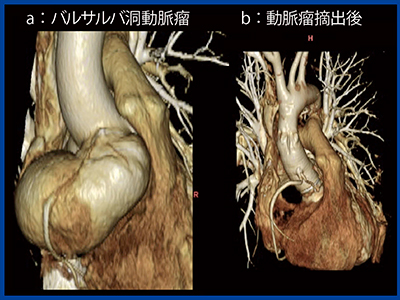

図2は,2つの大きなバルサルバ洞動脈瘤のある症例で,右冠動脈(RCA)基部の動脈瘤は特に大きく拍動性にRCAを圧排していたが(a),PhyZiodynamicsを適用した術後の画像では圧排の程度が改善していることが明瞭である1)(b)。

図2 バルサルバ洞動脈瘤症例におけるPhyZiodynamicsの有用性